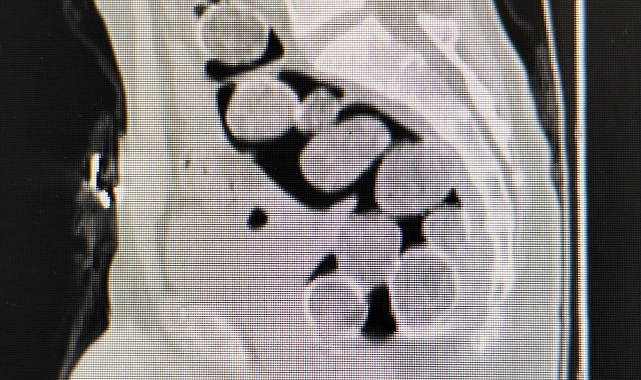

Samsun'a yutarak uyuşturucu madde sokmak isteyen 2 kişi ile onları otogarda karşılayan şahıs, polisin operasyonu sonucu yakalandı. Samsun Cumhuriyet Başsavcılığı koordinesinde, uyuşturucu madde ticareti yapan şahıslara yönelik yapılan çalışmalarda İl Emniyet Müdürlüğü Narkotik Suçlarla Mücadele Şube Müdürlüğü ekipleri, Samsun'a uyuşturucu naklettiğinden şüphelenilen ve Samsun otogarına gelen A.A(36) ve H.T.'yi (44) takibe aldı. Şahısların binmiş olduğu araç İlkadım ilçesi Kıran Mahallesi'nde durduruldu. Araçta bulunan şahıslar ve araç üzerinde yapılan aramada herhangi bir uyuşturucu madde bulunamadı. Şahısların yanlarında valiz, çanta veya eşya bulunmaması ve A.A. ve H.T.'nin halsiz, tedirgin ve şüpheli davranışlar sergilemeleri üzerine yutmak suretiyle bağırsaklarında ve midelerinde uyuşturucu maddeyi getirebileceği değerlendirilerek, Samsun Eğitim ve Araştırma Hastanesine sevklerine karar verildi. Hastanede çekilen röntgen filminde, mide ve bağırsaklarında yabancı maddeler olduğu tespit edilen A.A. ve H.T. gözaltına alındı.

A.A. ve H.T.'nin mide ve bağırsaklarına yapılan tıbbi müdahale sonucunda, 18 paket halinde toplam 500 gram metamfetamin ele geçirildi. Şüpheli şahısların ikametlerinde yapılan aramada ise 1 adet ruhsatsız tabanca ve 99 adet fişek elde edildi. A.A. ve H.T.'nin yanı sıra onlara yardım ve yataklık ettiği tespit edilen R.K.(44) de polis ekiplerince gözaltına alındı.